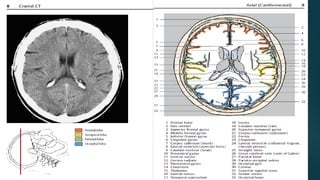

Este documento es el programa para un taller de imágenes del curso de emergencia 2015 impartido por el Dr. Víctor Delgado. El taller se centra en el uso de imágenes médicas para el diagnóstico y tratamiento de pacientes en coma traumático según la base de datos de Marshall. El Dr. Delgado es el único instructor repetido a lo largo del documento.